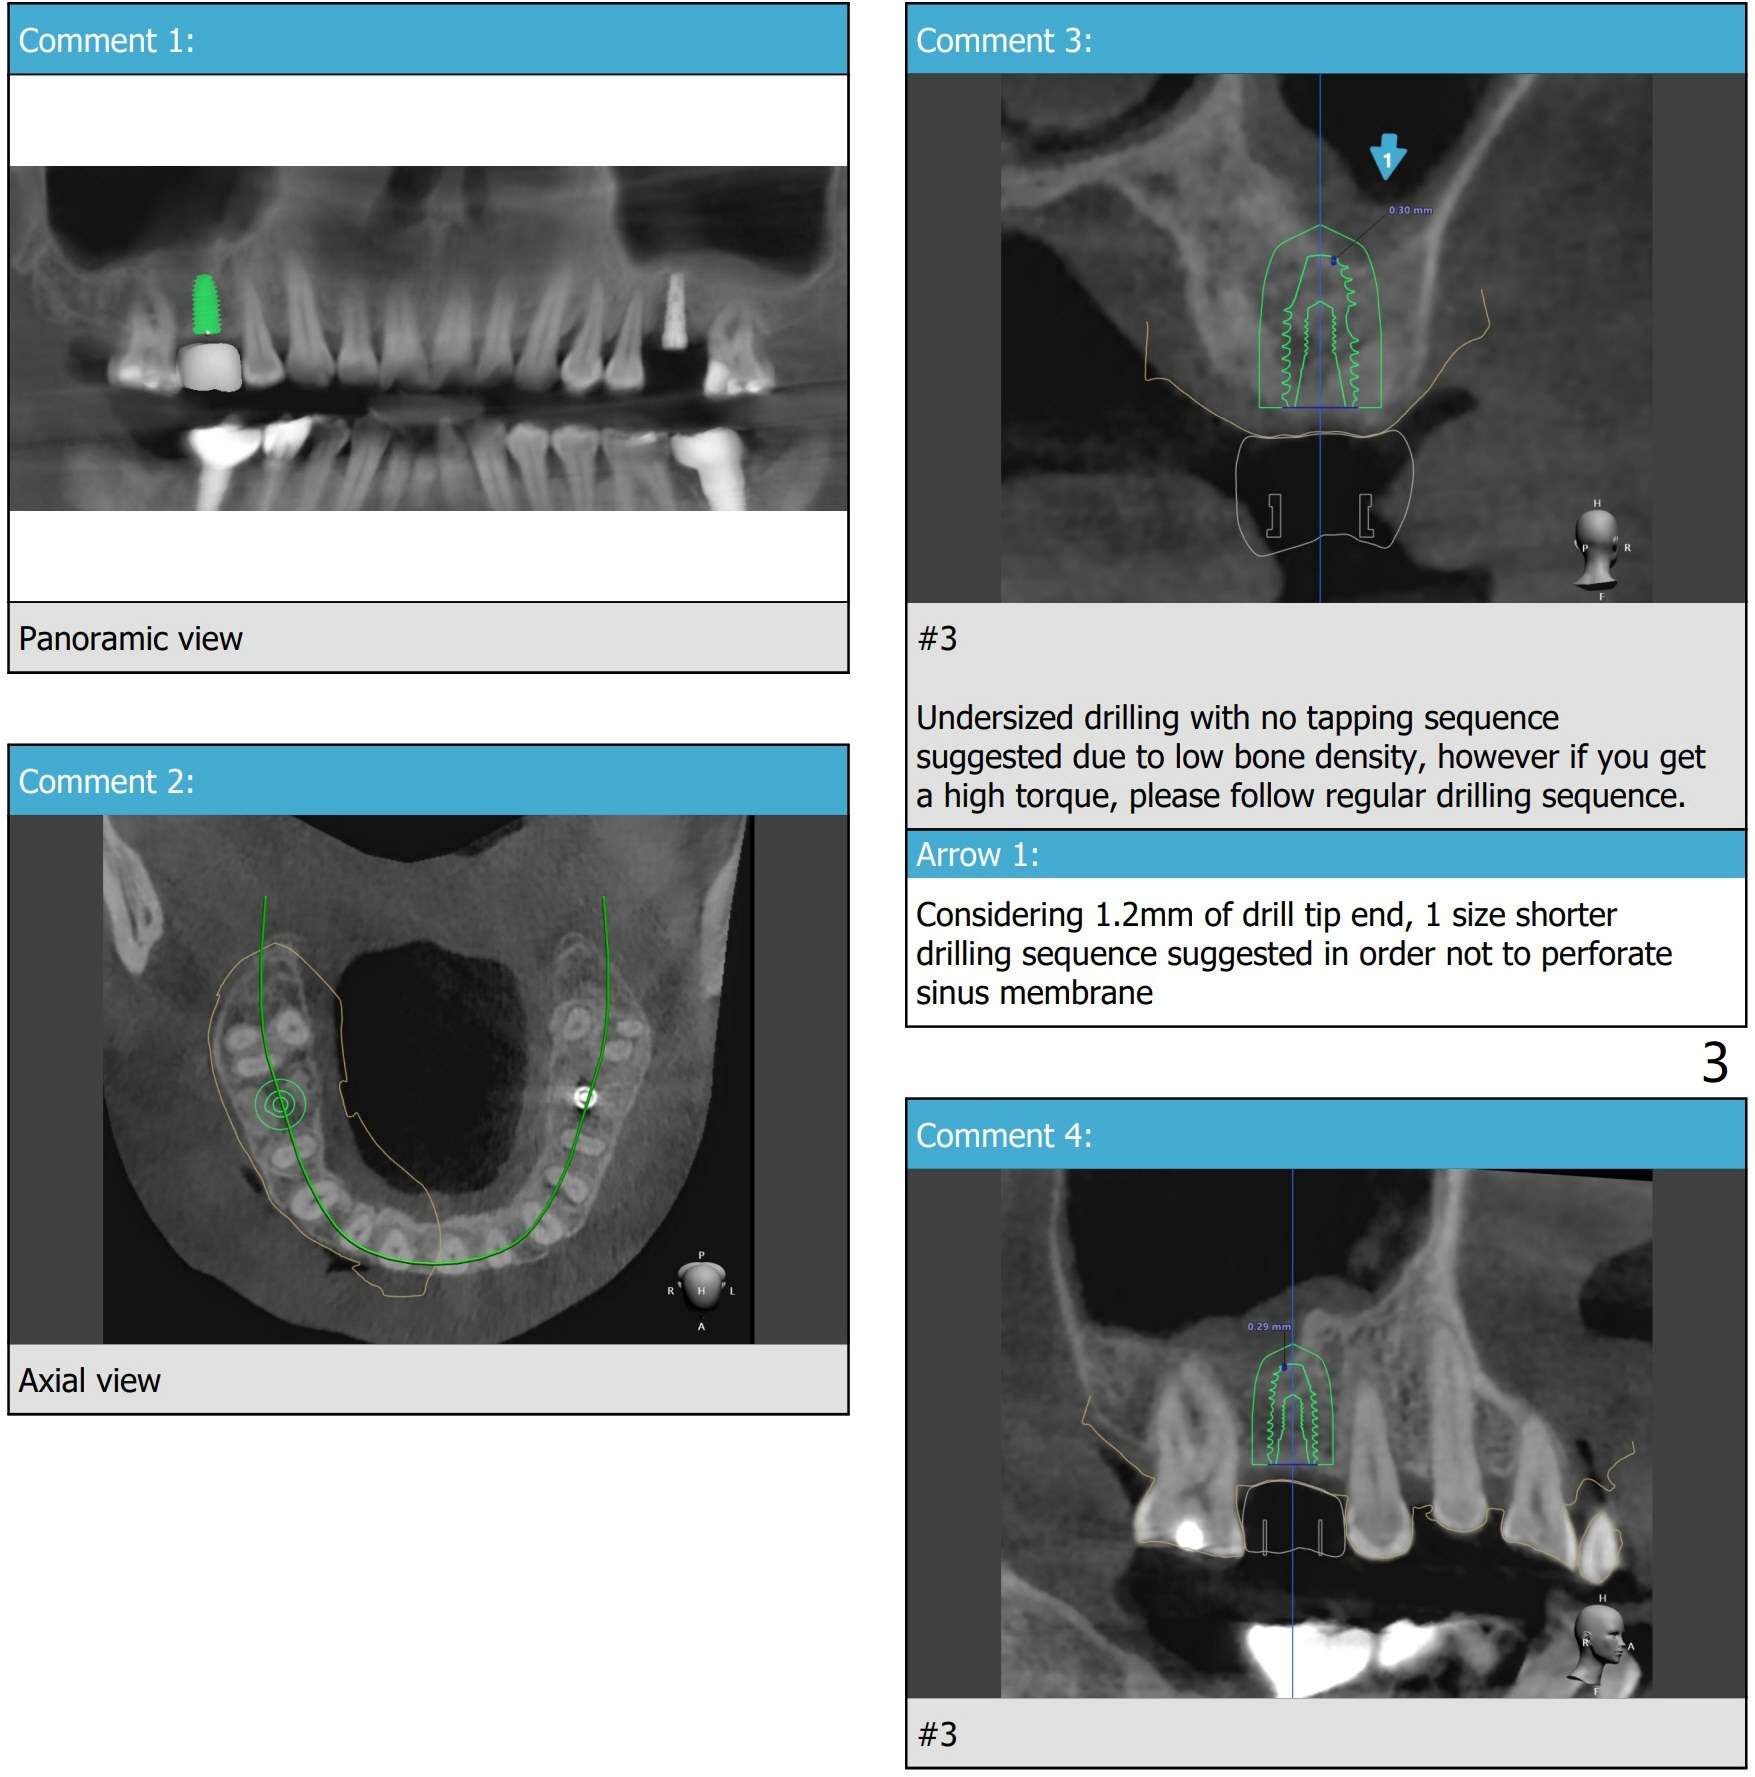

Wide Bone

A 52-year-old man requests implant at #3 and 31 a few months post socket preservation.

Xin Wei, DDS, PhD, MS 1st edition 08/02/2021, last revision 08/08/2021